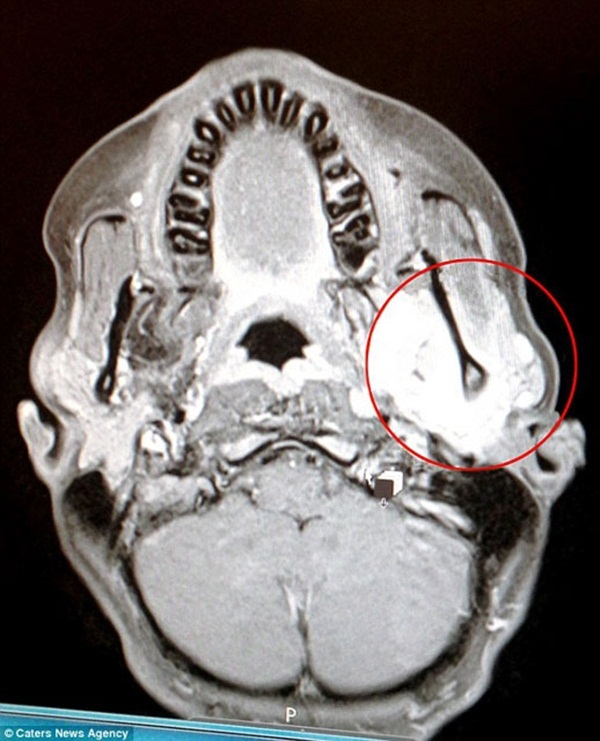

Doktora giden Nadia'nın çenesinin detaylı MR'ı çekilince aslında genç kızda kanser olduğu tespit edildi.

Acilen kemoterapi tedavisine başlayan genç kızda nadir görülen bir tümöre rastlandı.